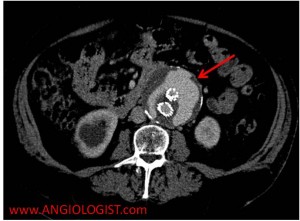

- Type II endoleak – Results from a blood vessel that is filling the original aneurysm sac around the graft. Three blood vessels that are commonly implicated in type II endoleak are lumbar arteries, accessory renal arteries and the inferior mesenteric artery. An important principle to understand regarding type II endoleaks is that there should always be two arteries visible entering the aneurysm sac – one artery is the one carrying blood to the sac and the other taking it out (otherwise the sac would always grow and rupture).

Two signs during imaging suggest an endoleak. The first is continued aneurysm expansion despite treatment. The second is extravasation of contrast material from within the artery (or graft) into the aneurysm sac. When this occurs the type of endoleak needs to be delineated. This is done by examining the endoleak location, looking for a blood vessel entering the aneurysm sac and making sure the stent is complete (without overt flaws in the stent). Another tip for proper CT imaging of endoleak is to use delayed images (typically at 70 seconds after contrast injection). At this time equilibrium has been achieved. A common mistake is mistaking calcifications and contrast extravasation on CT. Therefore a comparison of the contrast and non-contrast images should be made.